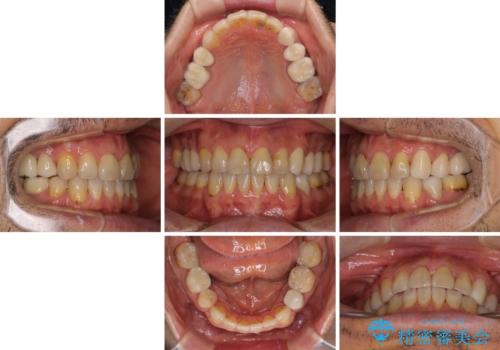

- むし歯による奥歯の痛みを気にして来院された患者様です。

神経にまでむし歯の及んでいる歯や、既に根管治療がされている歯に痛みがあったため、まずは根管治療を行うこととしました。

その後、以前行った抜歯矯正の後戻りをインビザライン・ライトにより改善し、むし歯や銀歯はオールセラミッククラウンにて補綴治療することとしました。

痛みは速やかに引き、銀歯や黒く変色したむし歯がセラミッククラウンで自然な色合いに仕上がり、患者様には大変満足していただきました。